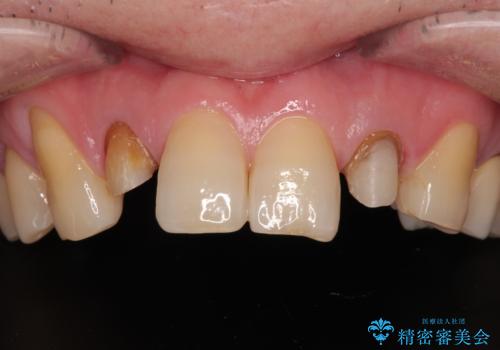

前歯の色味を治したい オールセラミッククラウン

- 前歯の色味が気になるとのことで来院された患者様です。左上の2番目の歯の歯茎のラインと被せものの境目の適合が悪い状態だったのでオールセラミッククラウンによる補綴治療を行っていくことになりました。

見た目、機能面共に満足していただけました。

右上2番目の歯の違和感もなくなったと喜んでいただけました。